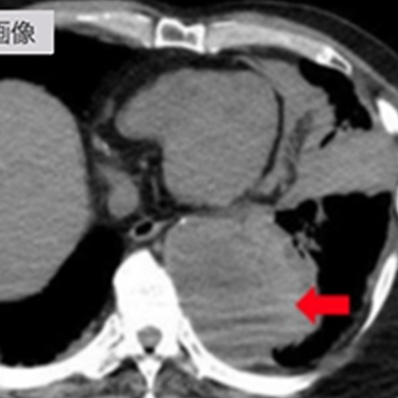

急性大動脈解離

(StanfordA型)